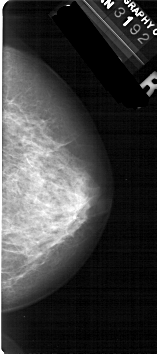

A_1130_1.RIGHT_MLO

RIGHT_MLO LINES 5491 PIXELS_PER_LINE 2791 BITS_PER_PIXEL 12 RESOLUTION 43.5 NON_OVERLAY